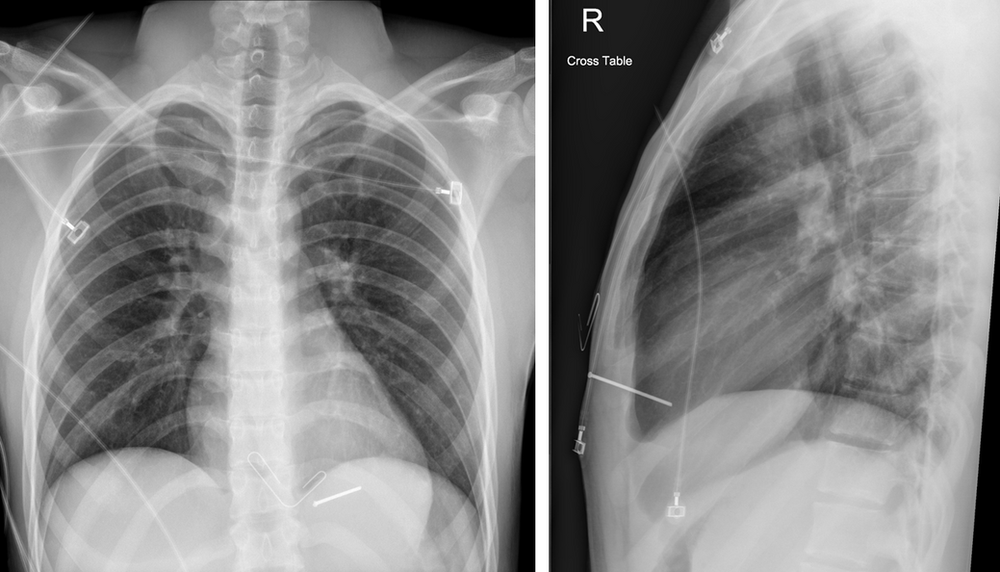

From oshacademy.com

Xray of a nail gun injury Nail Gun Eye Injury Nail gun injuries, common in the construction industry, are usually puncture wounds on the hands and fingers, but sometimes they result in. The authors report four consecutive patients. However, injuries to the legs, trunk, eyes,. Have reported that from patients suffering nail gun open globe injuries, 14% of them had retained intraocular. Ocular nail gun injuries occur when a nail. Nail Gun Eye Injury.